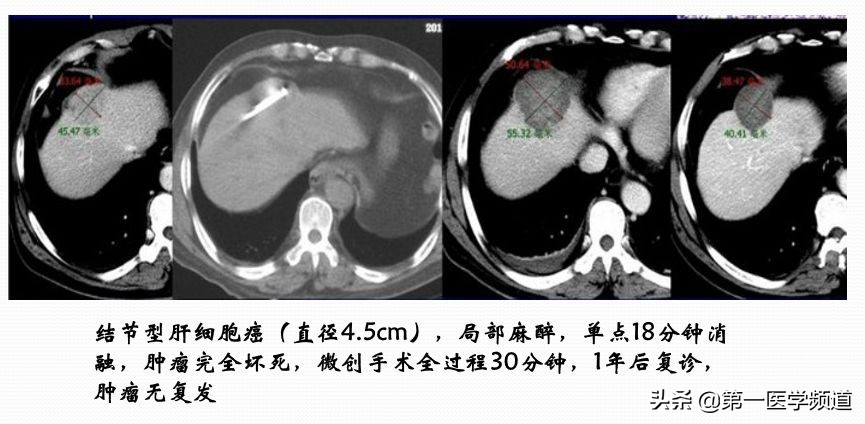

微波手术相对消融来说,比较简单,因为大部分的病人都是单针的处理,在临床上用得也非常广泛,比如应用于肝癌、肺癌、乳腺癌、胰腺癌、前列腺癌、骨肿瘤、子宫肌瘤等。它安全性比较高,而且价格适中。

这是一个典型的微波治疗肝癌患者的案例。肝脏内比较大的肿块,接近5cm左右,我们通过8个位点做消融治疗,取得比较好的效果,术后肿瘤完全坏死。